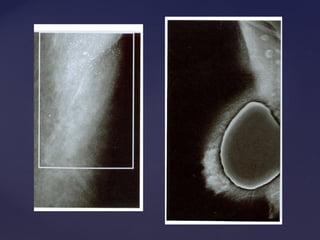

Padrão mamográficoPadrão mamográfico

Descrição Acurácia Diagnóstica

Lipossubstituídas (até 25% de tecido

glandular)

Muito alta

Parcialmente lipossubstituídas (26 a 50% de

tecido glandular)

Alta

Densas e heterogêneas

(51 a 75% de tecido glandular)

Limitada

Muito densas (>75% de tecido glandular) Limitada

Padrão mamográficoPadrão mamográfico DescriçãoAcurácia Diagnóstica Lipossubstituídas (até 25% de tecido glandular) Muito alta Parcialmente lipossubstituídas (26 a 50% de tecido glandular) Alta Densas e heterogêneas (51 a 75% de tecido glandular) Limitada Muito densas (>75% de tecido glandular) Limitada